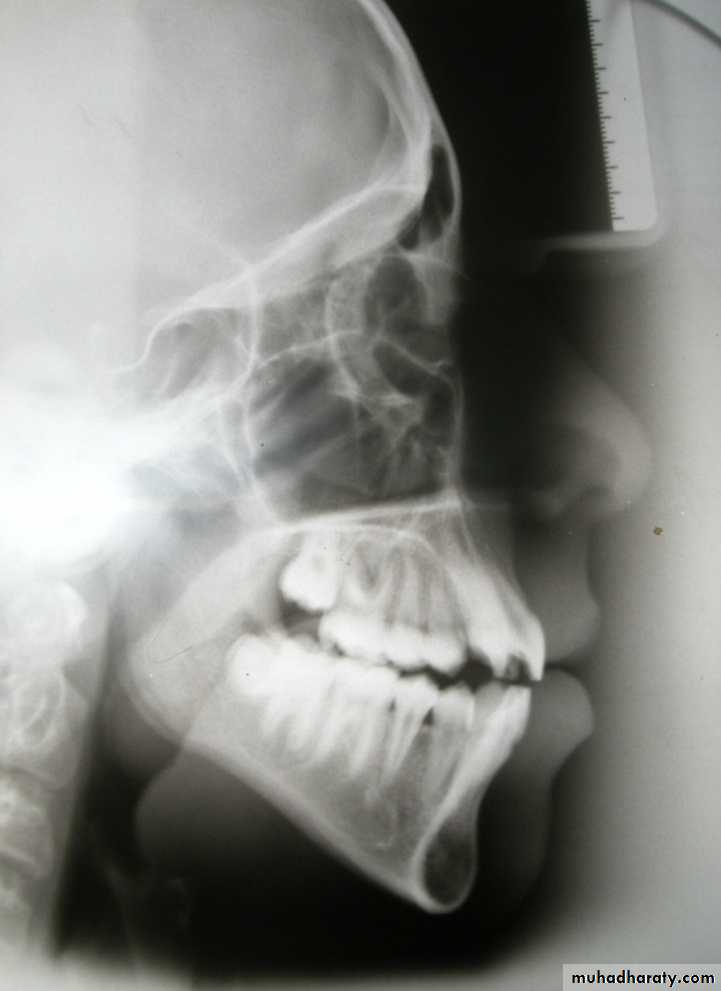

Growth EvaluationSuperimposition on cranial base structures:

To examine overall changes in the facial pattern including changes in maxilla and mandible in relation to the cranial base

It is made on:

1- De Coster line2- SN line